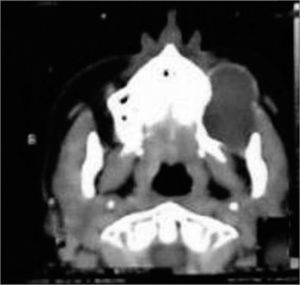

Computed tomography of the middle third of the face showed an osseous cyst with dense content, measuring about 6.0 cm along its longest dimension, located deep in the left maxillary sinus next to the lateral wall of the left maxillary bone; the dental alveoli were involved (Fig. 1).